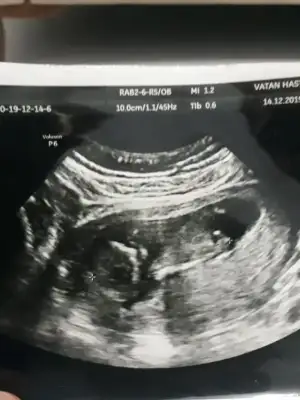

Doğru yere mi yazdım bilmiyorum ama benim bebeğime de bakar mısınız Kızlar 14 haftalık görüntü

Kızlar 14 haftalık bu sizce nedir